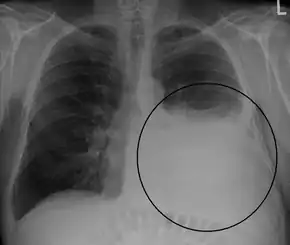

A pleural effusion appears as an area of whiteness on a standard posteroanterior chest X-ray.[9] Normally, the space between the visceral pleura and the parietal pleura cannot be seen. A pleural effusion infiltrates the space between these layers. Because the pleural effusion has a density similar to water, it can be seen on radiographs. Since the effusion has greater density than the rest of the lung, it gravitates towards the lower portions of the pleural cavity. The pleural effusion behaves according to basic fluid dynamics, conforming to the shape of pleural space, which is determined by the lung and chest wall. If the pleural space contains both air and fluid, then an air-fluid level that is horizontal will be present, instead of conforming to the lung space.[10] Chest radiographs in the lateral decubitus position (with the patient lying on the side of the pleural effusion) are more sensitive and can detect as little as 50 mL of fluid. At least 300 mL of fluid must be present before upright chest X-rays can detect a pleural effusion (e.g., blunted costophrenic angles).

Massive left-sided pleural effusion (whiteness) in a patient presenting with lung cancer.

Massive pleural effusion, later proven to be hemothorax